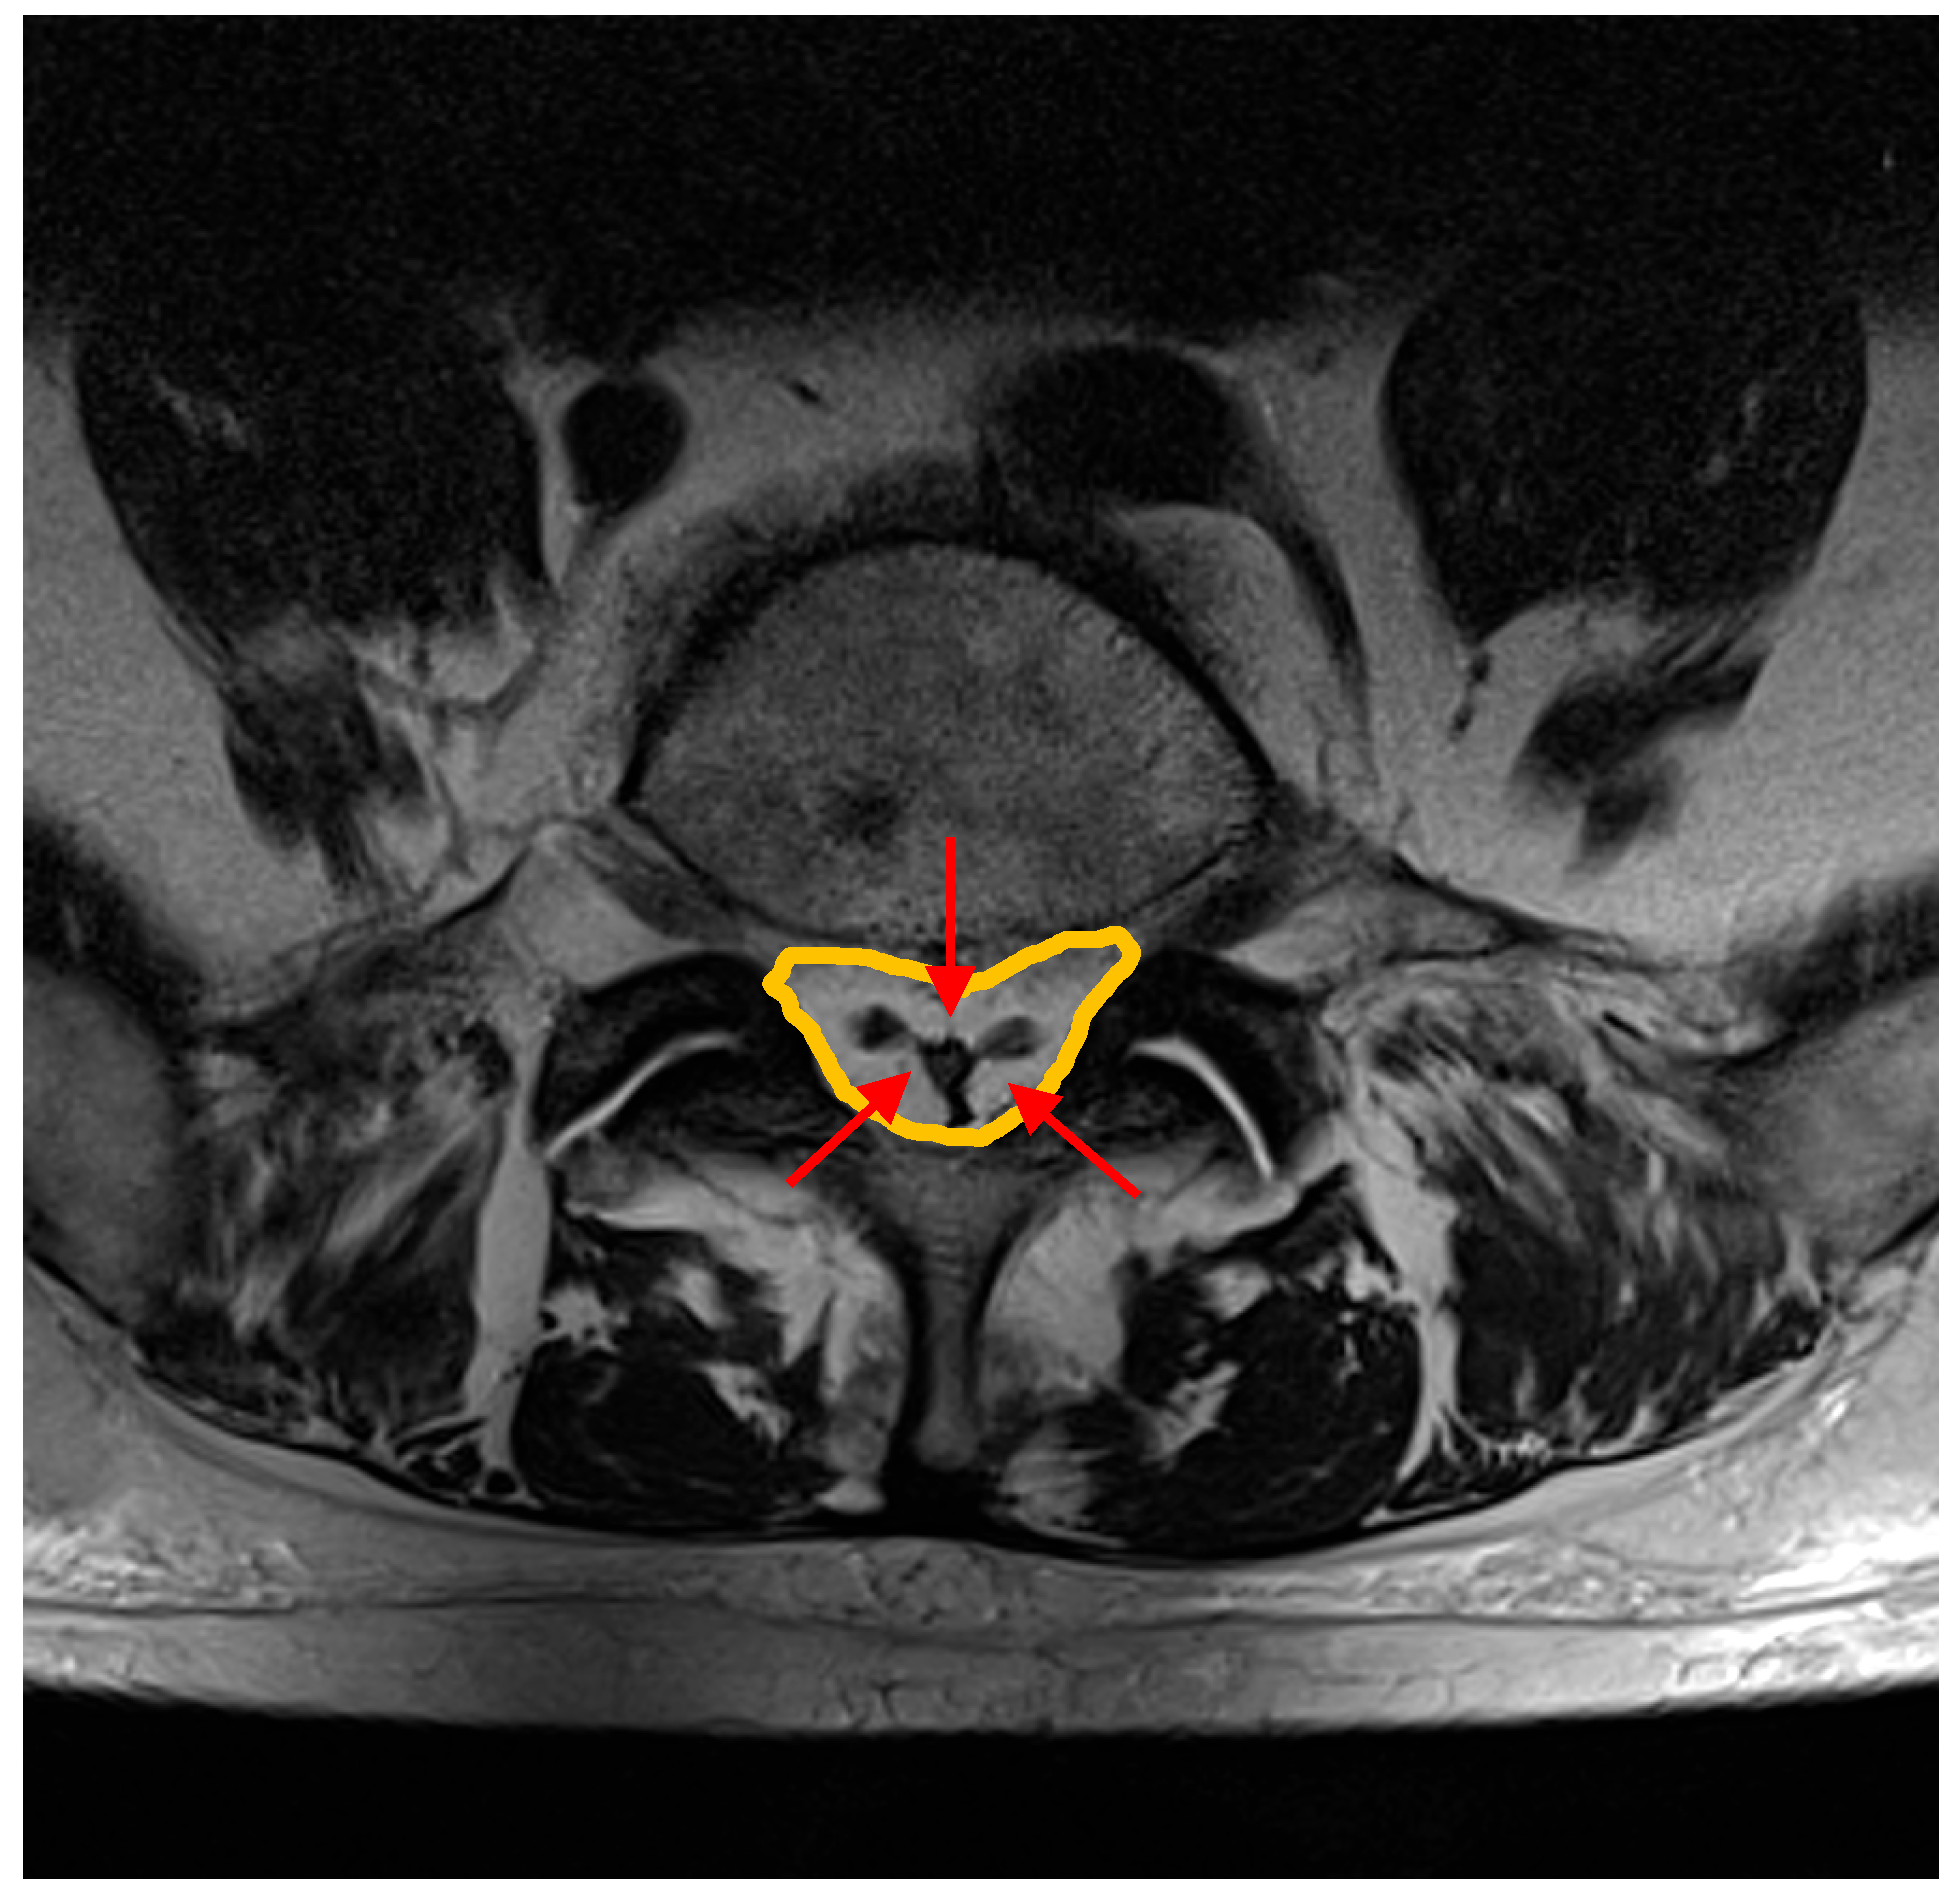

- VAT anterior–posterior max diameter at L3 level represented by the distance between the abdominal muscular fascia and the anterior wall of the abdominal aorta at the L3 vertebral level; MR-localizer sequences were used to achieve this aim (Figure 2, panel B).